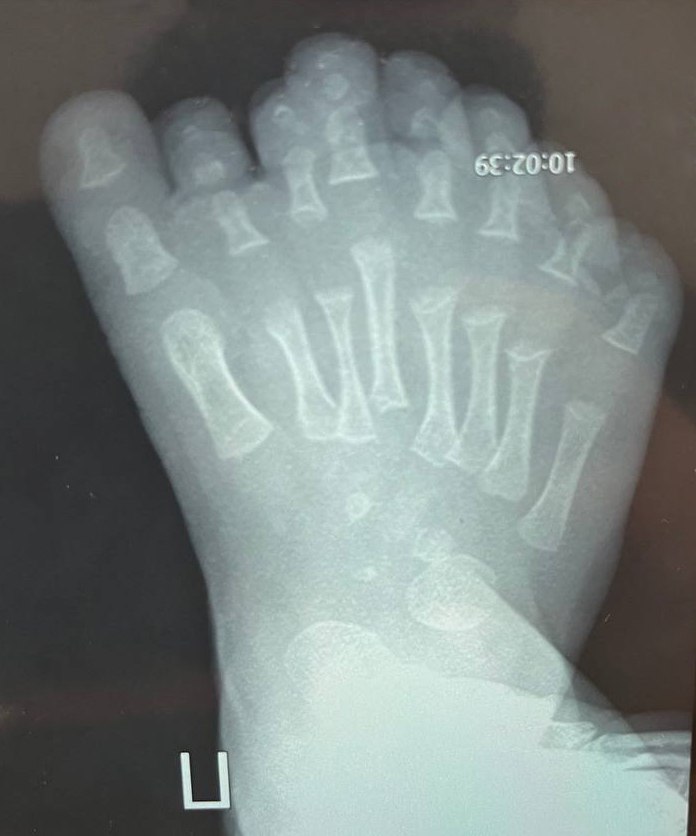

Ребенок родился с восьмью пальцами на ноге.

Такая патология называется полидактилией, она приводит к нарушению развития стопы. Чтобы избежать негативных последствий, врачи Ивано-Матренинской детской клинической больницы провели сложную операцию.

По словам врача травматолога ортопеда Ильи Зеленина, особенность полидактилии у пациента заключалась в том, что было увеличено не только количество фаланг пальцев, но и количество плюсневых костей.

Операция была сложная, перевязки проводят каждый день. Малыш останется под наблюдением врачей ещё долго. Сейчас ребенку семь месяцев, и как раз летом он сможет сделать свои первые шаги.

— К году стопа должна полностью зажить, кости — перестроиться и встать на свое определенное природой место, — говорит Илья Зеленин.